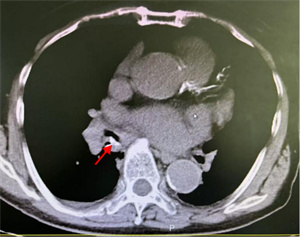

鲜美的动物骨髓深受很多人喜爱。一位中年患者清晨急匆匆来到我院呼吸科住院部。主诉前一天晚餐吸食猪骨髓时,不慎将食物吸入气管,出现反复剧烈咳嗽,并有咯血。我院呼吸科医生在其急诊胸部CT中发现右中间段支气管有一 “刀片样异物” 横在管腔内。评估病情并做好预案后,医生顺利取出一锐利骨片异物,有效阻止了 “利器” 造成肺内出血恶果的发生。